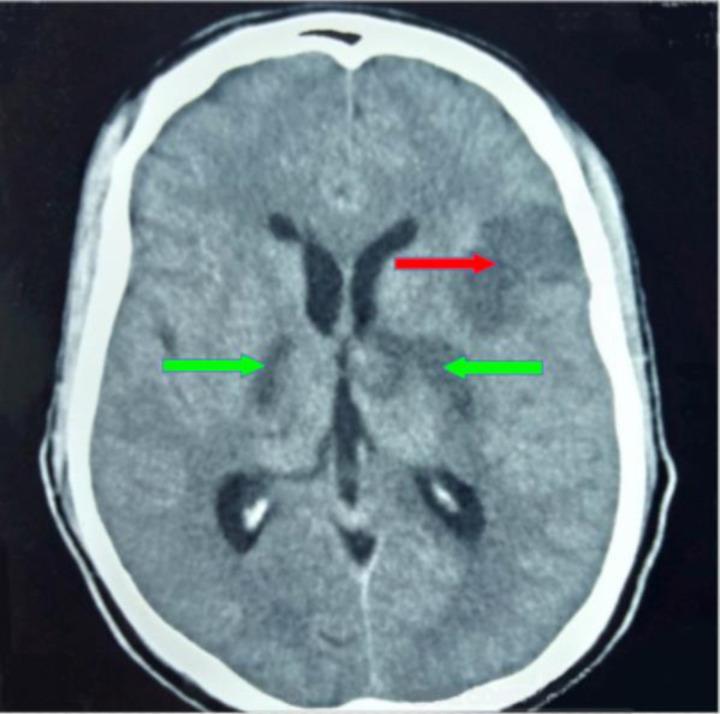

Computed tomography patterns of intracranial infarcts in a Ghanaian tertiary facility.

About 50.6% of the study participants were females with an average age of 62.59±13.91 years. Males were affected with ischaemic strokes earlier than females (0.001). The risk factors considered were, hyperlipidaemia (59.5%), hypertension (49.0%), Type 2 diabetes mellitus (DM-2) (39.6%) and smoking (3.0%). The three commonest ischaemic stroke CT scan features were wedge-shaped hypodensity extending to the edge of the brain (62.8%), sulcal flattening/effacement (57.6%) and loss of grey-white matter differentiation (51.0%), which were all significantly associated with hypertension. Small deep brain hypodensities, the rarest feature (2.2%), had no significant association with any of the risk factors considered in the study.

约 50.6%的研究参与者为女性,平均年龄为 62.59±13.91 岁。男性比女性更早受到缺血性中风的影响(0.001)。考虑的危险因素有高脂血症(59.5%)、高血压(49.0%)、2 型糖尿病(DM-2)(39.6%)和吸烟(3.0%)。三种最常见的缺血性中风 CT 扫描特征是楔形低密延伸至脑边缘(62.8%)、脑沟变平/消失(57.6%)和灰白质分界丧失(51.0%),这些都与高血压有显著关联。最小的深部脑低密灶是最罕见的特征(2.2%),与研究中考虑的任何危险因素都没有显著关联。